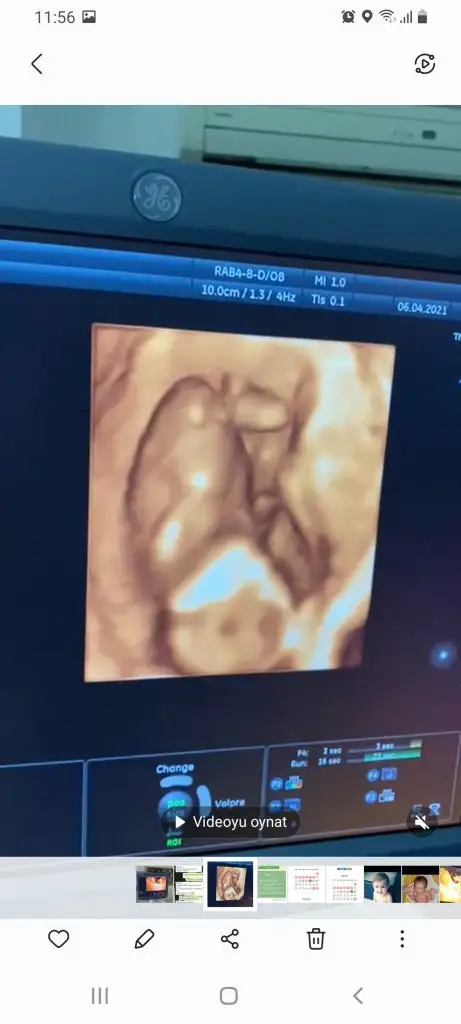

Anladım sanırım o dqer bacaqının qörüntüsü 3 hafta sonra kesin belli olacaqını düşünüoruz 16 haftalık olucak ozman söylerim cinsiyetni inş nasipseÇok karanlık emin olamadım ama tahminim var Erkek sanki

Üstte çizdim orası bacak gibi görünmedi okla gösterdiğim yer nub gibiAnladım sanırım o dqer bacaqının qörüntüsü 3 hafta sonra kesin belli olacaqını düşünüoruz 16 haftalık olucak ozman söylerim cinsiyetni inş nasipse

Kız görünüyorEki Görüntüle 2826055

Tekrar USG paylaşın demiştiniz 12+5 günlük burada doktor bir tahmin yapmadı ne düşünüyorsunuz :)Ikra meyra

Kız görünüyorIkra meyra bana 11 haftalikken kız demiştiniz. Şimdi 12 haftalik kontrolden geldim. Doktor bacak arasini da çekti ama hiç tahminde bulunmadı. Sizce hala kız mı?

Bacak arasi dolu gibi ya herkes erkek dedi o yüzden. Bacak arası böyle olup yine kız olabiliyor muuKız görünüyor

Bu gercekten daha doluOmu doluo dolu ise bu nedir 13 haftaEki Görüntüle 2826253